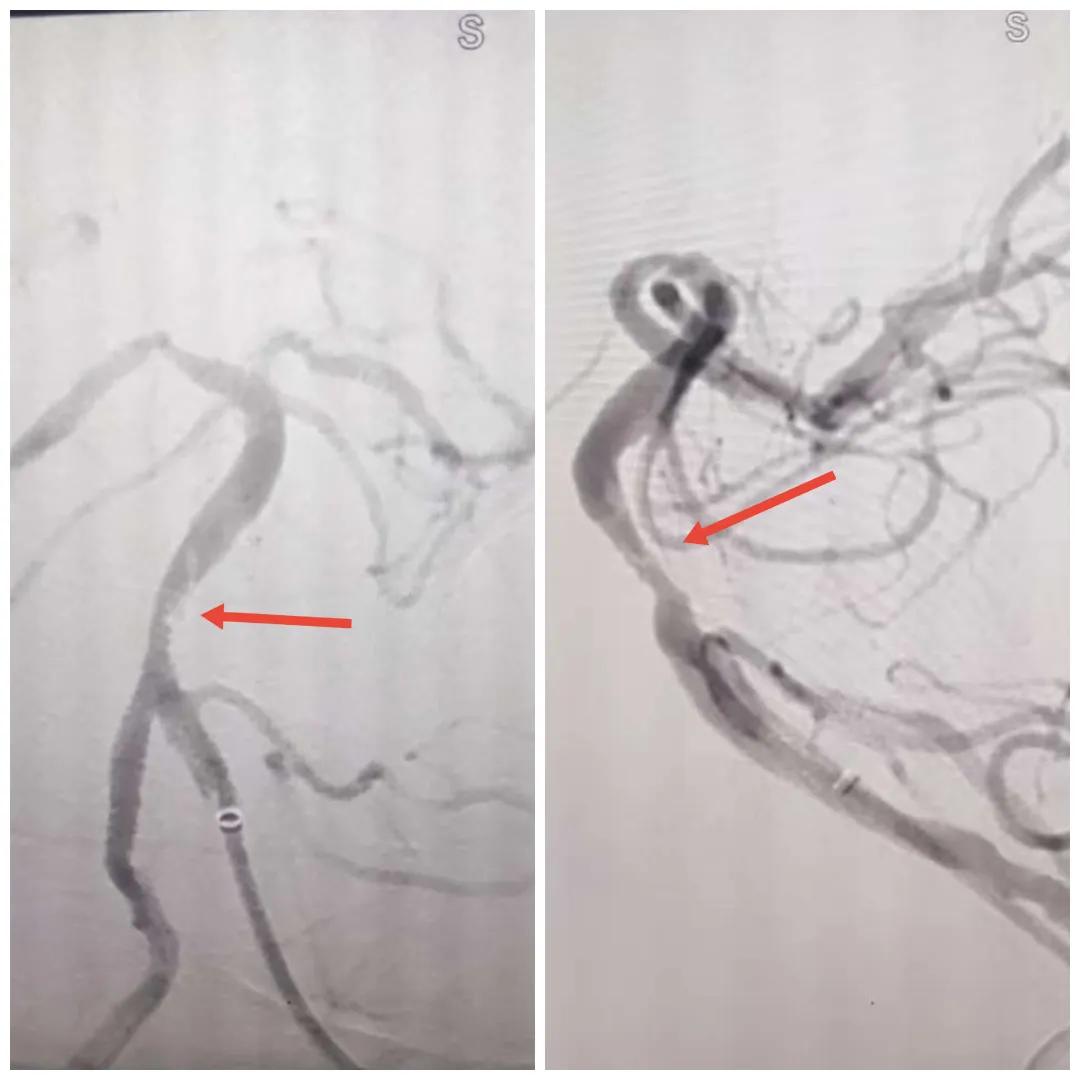

在經(jīng)造影后,主刀醫(yī)生腦一科副主任楊慶堂發(fā)現(xiàn)患者基底動(dòng)脈下段重度狹窄且狹窄段以遠(yuǎn)有大負(fù)荷血栓,其狹窄處考慮為動(dòng)脈夾層,手術(shù)難度及風(fēng)險(xiǎn)較大。楊慶堂副主任在彭壯副主任醫(yī)師的協(xié)助下運(yùn)用spaceman(太空人)技術(shù),中間導(dǎo)管抵近血栓抽吸配合支架拉栓,成功開(kāi)通血管。再次造影可見(jiàn)基底動(dòng)脈管腔明顯增寬,遠(yuǎn)端血管顯影良好,且等待20分鐘后造影仍顯示血流通暢。楊慶堂副主任考慮到本次手術(shù)時(shí)間不宜過(guò)長(zhǎng),現(xiàn)患者基底動(dòng)脈及分支前向血流維持良好,給予其抗栓藥物應(yīng)用后結(jié)束手術(shù),并建議患者3個(gè)月后復(fù)查造影,明確其基底動(dòng)脈夾層情況。

造影可見(jiàn)血管夾層和大量血栓形成

取栓后血管管腔增寬,前向血流良好